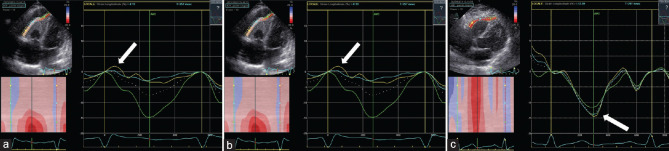

Hypereosinophilic syndrome (HES) is a systemic disorder with various manifestations, characterized by hypereosinophilia and caused by primary or secondary conditions. Loeffler's endocarditis (LE) represents a frequent cardiac manifestation of HES, caused by infiltration of the myocardium by eosinophilic cells, which determines endocardial damage, with subsequent inflammation, thrombosis, and fibrosis of either one or both ventricles. The diagnosis of cardiac involvement is based on a multimodality approach (i.e., two-dimensional transthoracic echocardiography [2D-TTE], speckle-tracking echocardiography [STE], and cardiac magnetic resonance [CMR]), with different findings depending on the stage of disease. STE may be useful in the initial phase when traditional imaging techniques may result negative, whereas CMR allows myocardial tissue characterization along with a better definition of the right ventricle. We present a rare case of LE with isolated right ventricular involvement in a patient with HES caused by chronic eosinophilic leukemia with constitutively activated fusion tyrosine kinase on chromosome 4q12, successfully treated with imatinib mesylate.